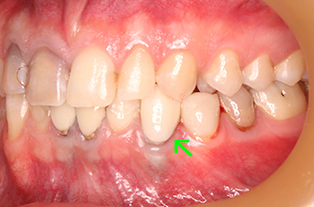

ジルコニアボンド

の症例

| 年齢・性別 | 20代・女性 |

| 主訴 | 右上1の審美障害 |

| 治療内容 | ジルコニアボンド |

| 治療期間 | 1ヶ月 |

| 治療費用 | 165,000円 |

| 治療方針 | まずは仮歯を入れながら形、機能面を精査。 その後問題がなければ最終的な被せ物の 型取りと色合わせをしていき、 仮の接着剤で しばらく過ごしていただく。 日常生活に問題がなく、審美的にも満足して いただけたら最終的な接着剤で装着。 |

| 特記事項 | 仮歯の期間は患者さまのお口の中の状態で 変わってきます。 |

| 担当者所見 | 前歯をぶつけ、神経が死んでしまった ため黒くなってしまった症例になります。 元々の歯がかなり白く綺麗であったため 審美面での調整が難しいケースになりましたが 最終的に満足していただくことができました。 |